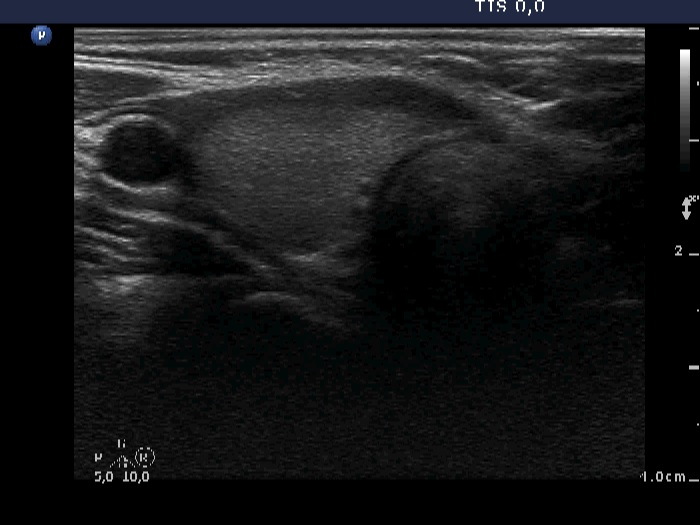

Two years after the initial examination (ultrasonographic picture 1)

Right lobe, horizontal scan. The lobe is echonormal.